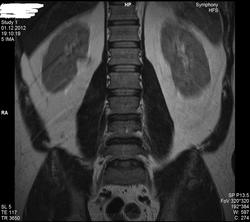

Уважаемые специалисты. МРТ после операции 8 нед.

Операция геминоламинэктомия L4-5 с установкой системы динамической стабилизации между остистыми 4-5.

После операции боли в пояснице прошли, боль в коленях и голенях осталась в неизменном виде. Ниже верхней трети голени боль не опускается.

По задней стороне туловища в ногах болей никогда не было. Уважаемый специалист, к сожалению не рентгенолог, утверждает что нет никаких признаков радикулопатии. Не посмотрите своим профессиональным взглядом.